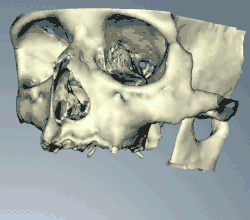

Success or failure of implants depends primarily on the thickness and health of the bone and gingival tissues that surround the implant,[2] but also on the health of the person receiving the treatment and drugs which affect the chances of osseointegration.[3][4][5][6][7][8][9][10] The amount of stress that will be put on the implant and fixture during normal function is also evaluated. Planning the position and number of implants is key to the long-term health of the prosthetic since biomechanical forces created during chewing can be significant. The position of implants is determined by the position and angle of adjacent teeth, by lab simulations or by using computed tomography with CAD/CAM simulations[11][12][13][14] and surgical guides called stents. The prerequisites for long-term success of osseointegrated dental implants are healthy bone and gingiva. Since both can atrophy after tooth extraction, pre-prosthetic procedures such as sinus lifts or gingival grafts are sometimes required to recreate ideal bone and gingiva.

When a more exacting plan is needed beyond clinical judgment, the dentist will make an acrylic guide (called a stent) prior to surgery which guides optimal positioning of the implant. Increasingly, dentists opt to get a CT scan of the jaws and any existing dentures, then plan the surgery on CAD/CAM software. The stent can then be made using stereolithography following computerized planning of a case from the CT scan. The use of CT scanning in complex cases also helps the surgeon identify and avoid vital structures such as the inferior alveolar nerve and the sinus.[49][50]: 1199